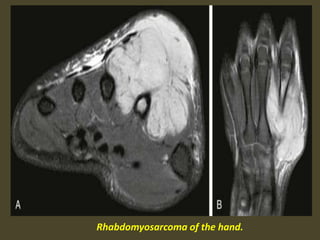

Rhabdomyosarcoma of the hand.